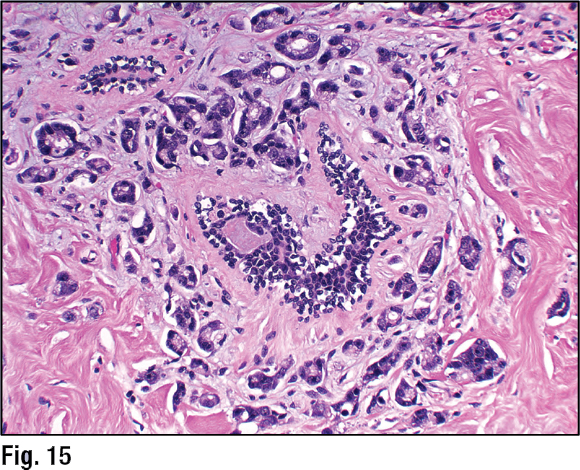

“Of course, when you look histologically, you should see there are just ducts and no lobules,” Dr. Collins added. But in some cases where there’s a lot of tumor, the pathologist needs to remember that the patient might be a male “and think of other differential diagnostic considerations.”

Dr. Collins showed an image of a carcinoma that had infiltrated around a benign duct in the patient’s breast (Fig. 15). Another duct in the middle of the image had a little proliferation, which she cautioned might be misconstrued as an in situ component. “In fact, it is just a little bit of hyperplasia,” she said. The tumor had “pleomorphic, highly atypical nuclei, and very prominent nucleoli in this particular case.” The patient had a history of prostate carcinoma. “PSA and PSAP testing confirmed this as an example of metastatic prostate carcinoma to the breast in a male patient.” (Fig. 16). —Karen Lusky